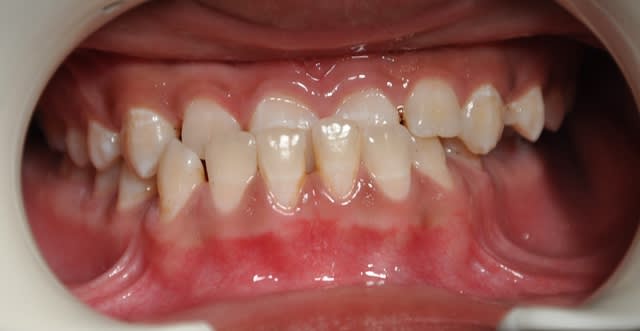

Il ne s'agit pas de faire confiance ou pas a l'examen clinique de notre ami(e)takamatika. Il s'agit d'une erreure tres ferequente que chacun de nous pourrait la faire surtout si la musculature a bien enregistrer cette deviation associee peut etre a une relle laterognathie. Je maintiens quand-meme mon point de vue car entre les deux series de photos (on ne sait pas combien de temps entre les deux), mais l'articule inversee au niveau de la canine inferieure/laterale sup cote droit a bien disparu, l'inverse d'articule anterieur n'est plus la et les lignes medianes dentaires se sont alignees!

Dans ce cas il y a une choses des deux: Soit la situation de depart etait en RC et le recentrage dentaire va creer un decentrage articulaire et comme disait ceramik les ATM n'aiment pas cette situation, ou bien (et c'est ce que je pense) la situation initiale etait en occlusion de convenance due a un contact premature au niveau de la canine/laterale et le simple fait de supprimer ce contact par le nivellement denatire a permis a la mandibule de se recentrer. Si des nouvelles radios de profil et de face sont a faire maintenant on ne doit pas voir le meme decalage condylien de depart et on peut quantifier le probleme d'origine squelettique.

Je suis désolé, mais ne suis pas d'accord avec toi, Saïd.

Tu as fait ta mesure de symétrie maxillaire/mandibule sur la panoramique qui est une radio prise en bout à bout incisives, cela enlève toute sa valeur.,

Pour moi, ce ne sont bien que les dents qui ont été déplacées. Les milieux incisifs ne se sont beaucoup améliorés et il est fortement vraisemblable que la 43 se soit lingualée.